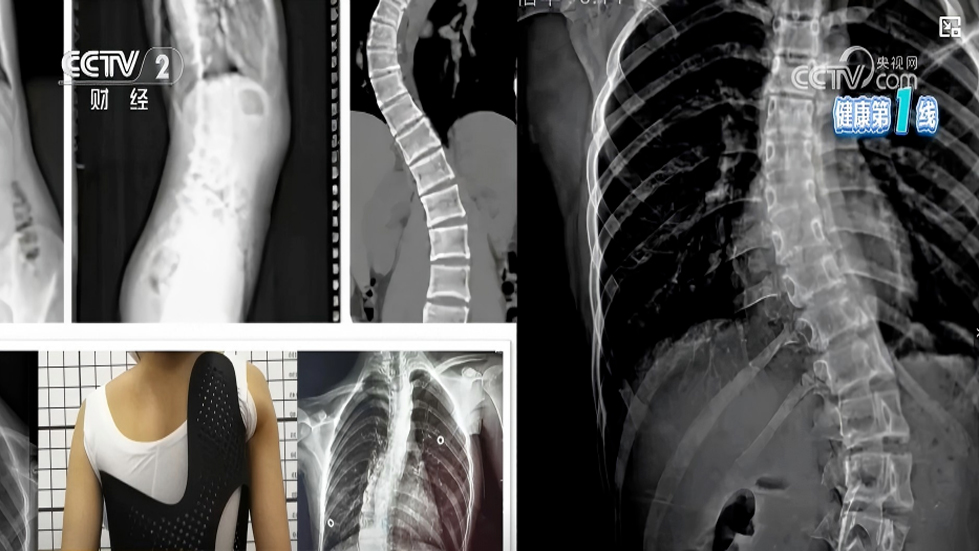

成功引进国际脊柱侧弯权威康复体系SEAS,获得意大利SEAS疗法认证并挂牌实践基

近日,我院康复医学科传来喜讯:为提高脊柱侧弯诊疗专业性,科室主任派出团队骨干成员,经过系统学习与严格考核,成功获得国际脊柱侧弯保守治疗领域的权威认证——意大利SEA...